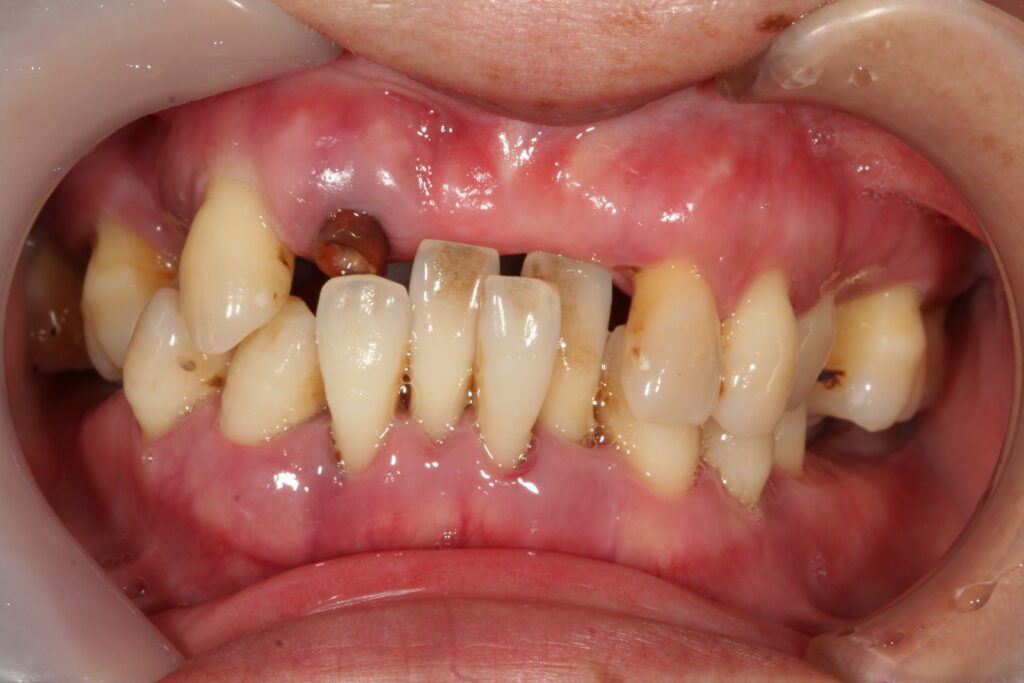

審美歯科 小城 2022.04.19 症例紹介 50代男性歯並びが悪くて食事がしにくいとずっと悩んでおられました。被せモノをして改善していきました。治療回数は2回でした。 症例紹介 久しぶりの更新です。前の記事 小城市倫理法人会次の記事